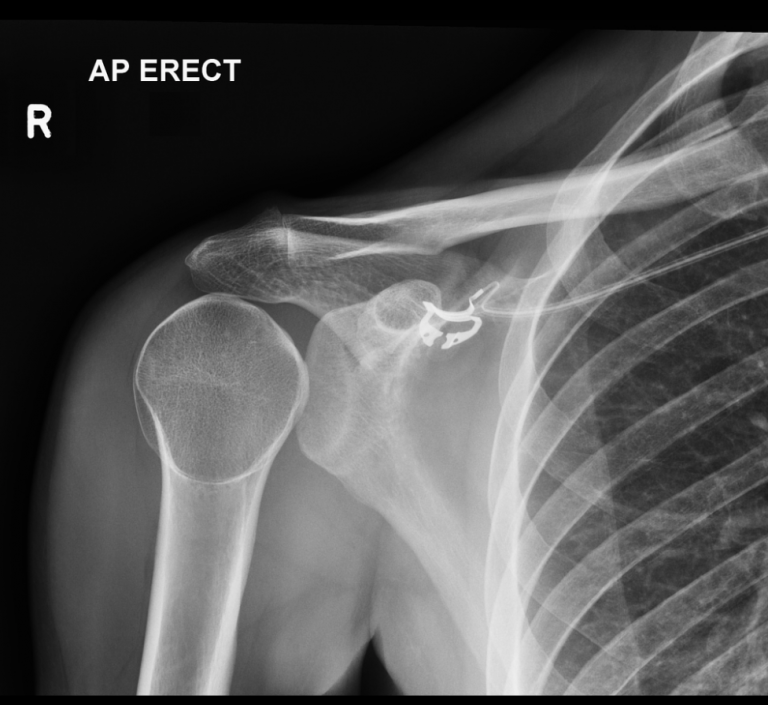

Shoulder XRay Right acromioclavicular joint dislocation radRounds Lateral X Ray Dislocation Of Shoulder As is an axillary view); Capturing images from different angles. Orthogonal to the ap shoulder (note: Shoulder dislocation is a term often used loosely to indicate dislocation of the head of the humerus from the glenoid of the scapula. This view is a pertinent. The shoulder can dislocate posteriorly, but. The lateral scapula shoulder or y view is part of. Lateral X Ray Dislocation Of Shoulder.

Emergency Medicine EducationEM3AM Posterior Shoulder Lateral X Ray Dislocation Of Shoulder Orthogonal to the ap shoulder (note: The lateral scapula shoulder or y view is part of the standard shoulder series. Shoulder dislocation (correctly termed a glenohumeral joint dislocation) involves separation of the humerus from the glenoid of. As is an axillary view); Be comfortable with multiple reduction techniques. Carefully review radiographs for posterior dislocations as they may appear “normal” on. Lateral X Ray Dislocation Of Shoulder.